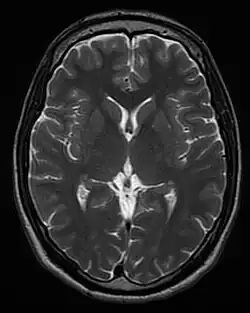

T1 and T2

Each tissue returns to its equilibrium state after excitation by the independent relaxation processes of T1 (spin-lattice; that is, magnetization in the same direction as the static magnetic field) and T2 (spin-spin; transverse to the static magnetic field). To create a T1-weighted image, magnetization is allowed to recover before measuring the MR signal by changing the repetition time (TR). This image weighting is useful for assessing the cerebral cortex, identifying fatty tissue, characterizing focal liver lesions, and in general, obtaining morphological information, as well as for post-contrast imaging. To create a T2-weighted image, magnetization is allowed to decay before measuring the MR signal by changing the echo time (TE). This image weighting is useful for detecting edema and inflammation, revealing white matter lesions, and assessing zonal anatomy in the prostate and uterus.